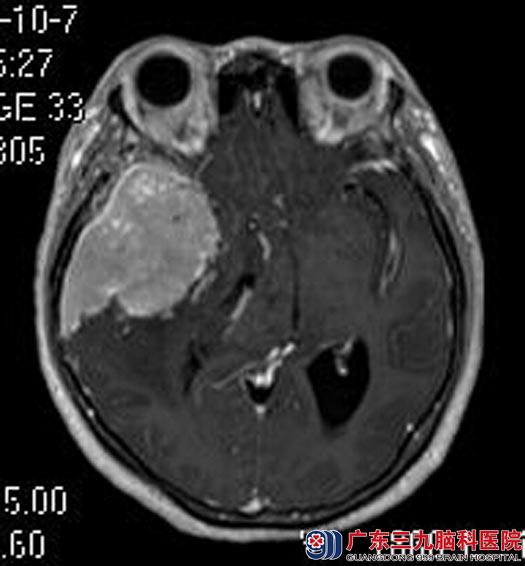

广东三九脑科医院进一步头颅MRI检查结果:右侧额颞部示一不规则形占位性病变,大小约为48.7mm×78.6mm×46.0mm;相应处脑组织明显受压,示大片状脑组织水肿影;右侧侧脑室受压变扁,环池变窄,中脑受压变形,左侧侧脑室轻度扩大,中线结构明显左偏,考虑巨大脑膜瘤,合并大脑镰下疝及右侧海马钩回疝形成。头颅CTA检查提示:右侧额颞部病变内可见少许小血管影,病变边缘可见较多的小血管影。